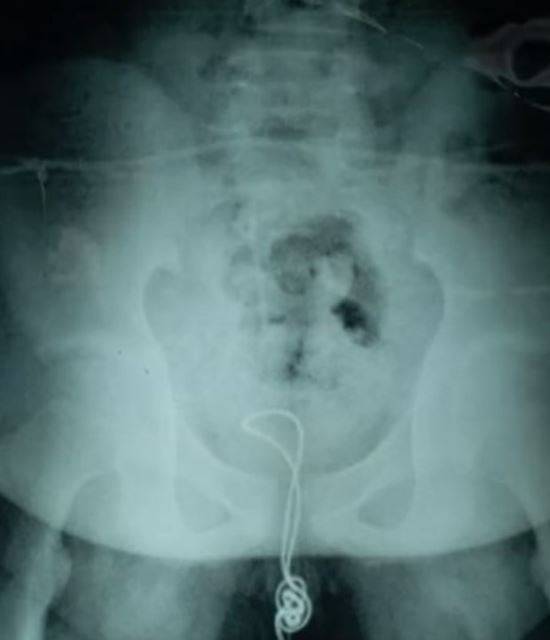

중국에 사는 10대 소년이 자신의 성기에 넣은 USB 케이블 매듭이 엉켜 빠지지 않는 사고가 발생해 수술을 받았다고 영국 메트로 등 외신이 5일(현지시간) 전했다. 이 소년은 케이블 제거 수술을 받고 지난 3일 퇴원했다.

매체에 따르면 A군(13)은 2주전쯤 긴 USB 케이블의 한쪽 끝을 잘라 20㎝ 가량을 자신의 성기에 집어 넣었다. 케이블은 방광에 닿으면서 엉키기 시작해 매듭이 생겼고, 빠지지 않았다. A군은 중국 북동부 헤이룽장성의 한 병원으로 긴급 후송됐다. 지역병원은 케이블을 빼내기 위해 소년의 성기와 케이블에 윤활제를 발랐지만 빼내지 못했다.

극심한 고통에 시달리던 A군은 다음날 하얼빈 아동 병원으로 이송됐다. 의료진은 소년의 방광을 잘라 그 속에 엉켜있던 케이블 매듭을 잘라냈다. 성기 속에 남아있던 나머지 케이블은 요도를 통해 빼냈다. 의료진은 “상태가 심각해 수술 외에는 방법이 없었다”고 당시 상황을 설명했다.